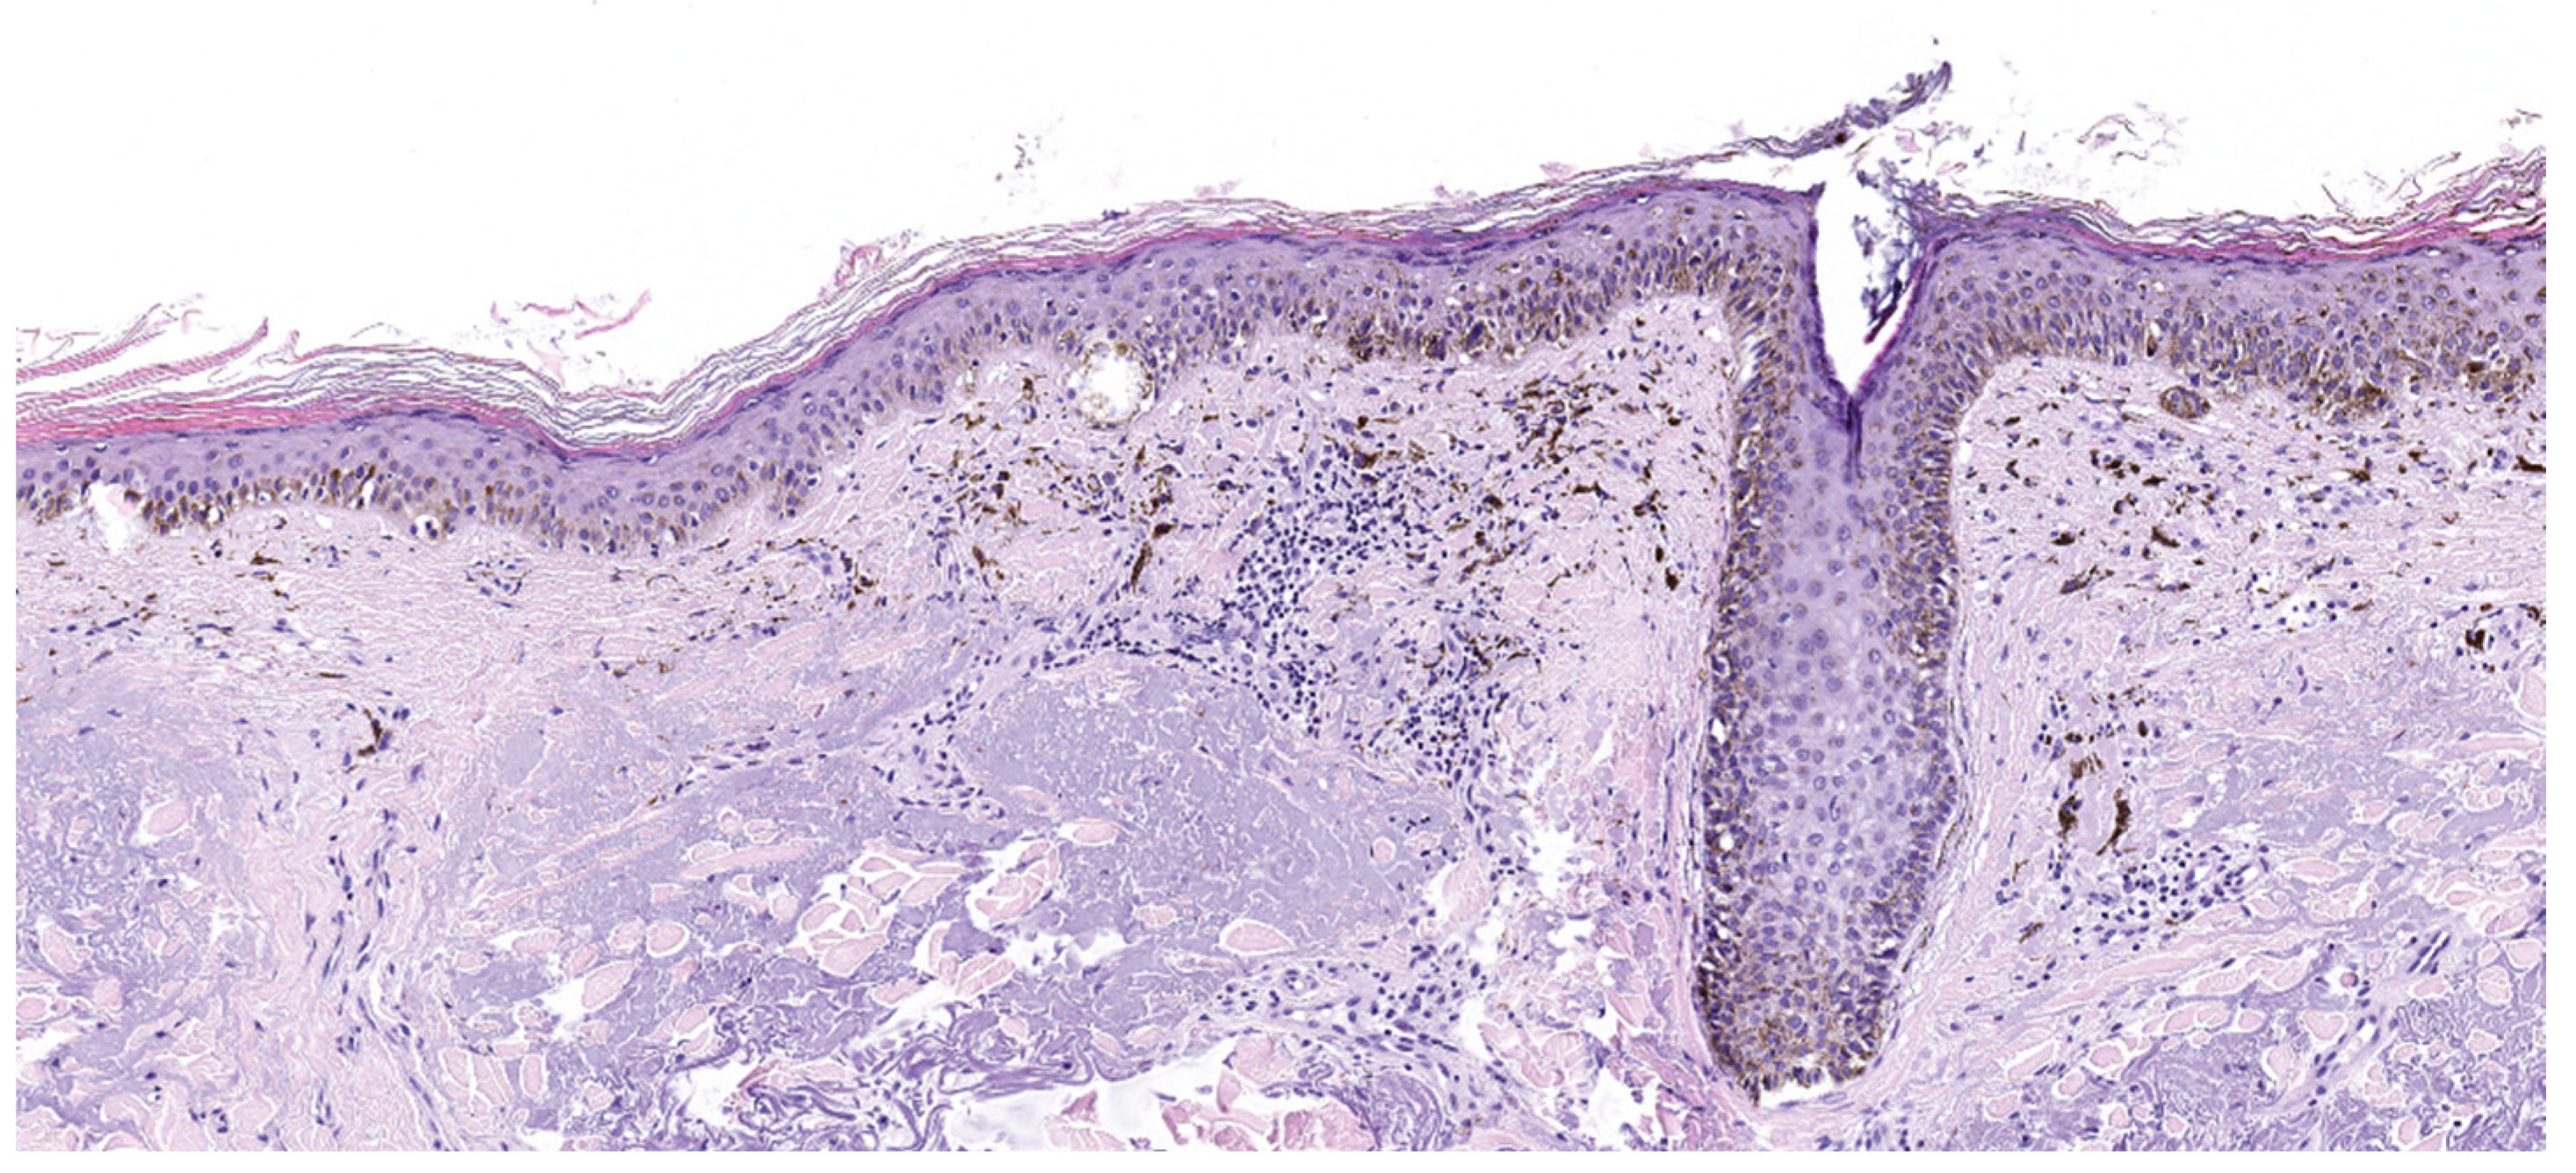

4.2. Lentigo Maligna Melanoma